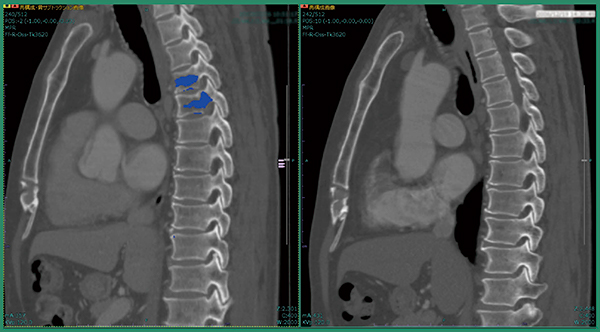

症例2も術後症例で,術前・術後の差分画像にてT10に骨転移が認められた。これは元画像でも比較的わかりやすいが,本症例はC7の椎弓にも造骨性の骨転移があることが差分画像で明瞭に示された(図5)。このような後方成分の小さな病変に対しては,ソフトウエアが特に役立つと考える。

図5 症例2:T10とC7椎弓への骨転移候補の検出